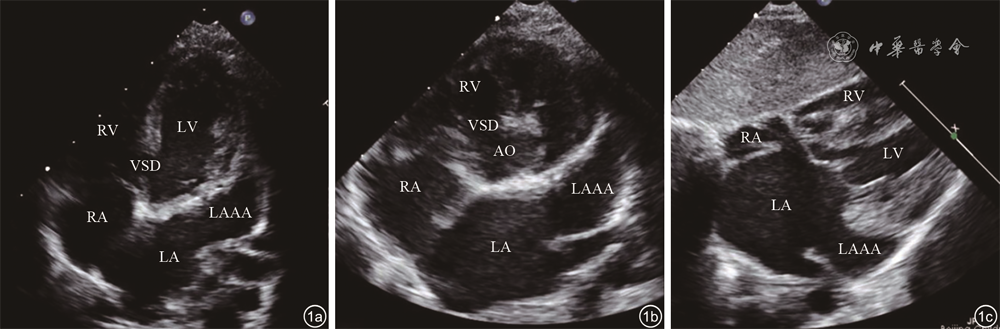

9例患者均经超声心动图检查诊断为LAAA,表现为:(1)四腔心、心底短轴、剑突下等切面二维超声图像可见左心室游离壁外囊状无回声结构,为LAAA;(2)LAAA与左心房交通(图1);(3)彩色多普勒可见LAAA与左心房间血流信号往返(图2);(4)巨大LAAA可压迫左心室或其他毗邻结构(图3);(5)同时可显示合并的其他占位性病变(图4)。

图1 左心耳瘤不同切面二维超声图像,可见左心室壁外侧囊状无回声区,与左心房交通,合并存在室间隔缺损。图a为心尖四腔心切面;图b为心底短轴切面;图c为剑突下四腔心切面